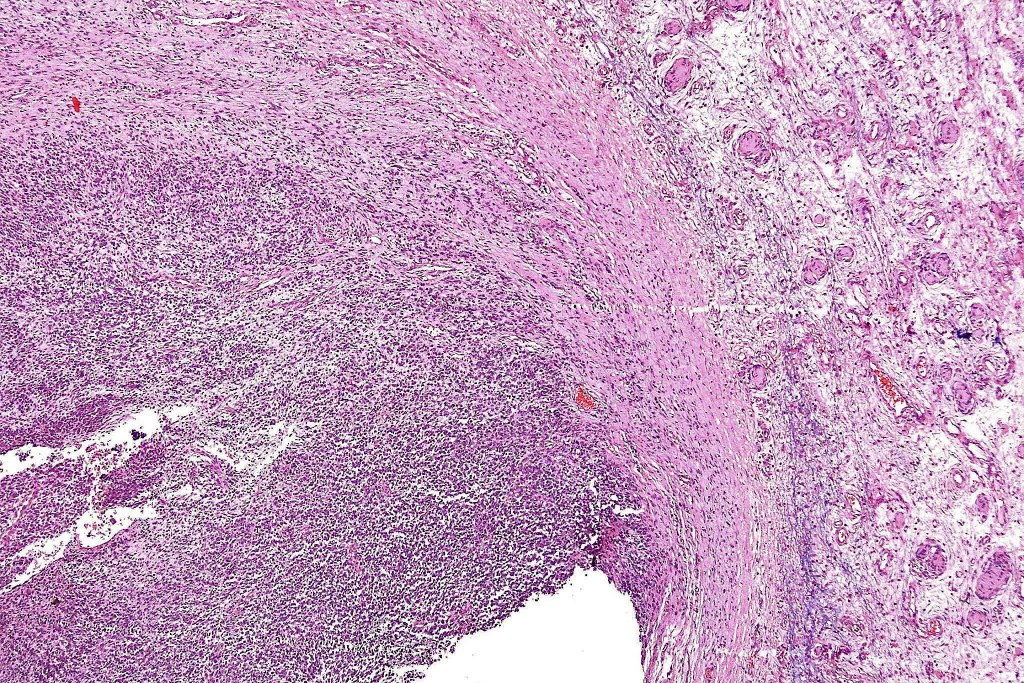

•The nodule generally merges with the adjacent nevus but sometimes it can be sharply circumscribed

•It is hypercellular and most often composed of epithelioid cells showing little pleomorphism & only occasional mitoses

•Some examples show more marked pleomorphism with prominent nucleoli and increased mitotic activity but abnormal mitoses are not a feature. These are not associated with any sinister biological potential

•Absence of necrosis, hemorrhage or Pagetoid spread in the overlying epidermis